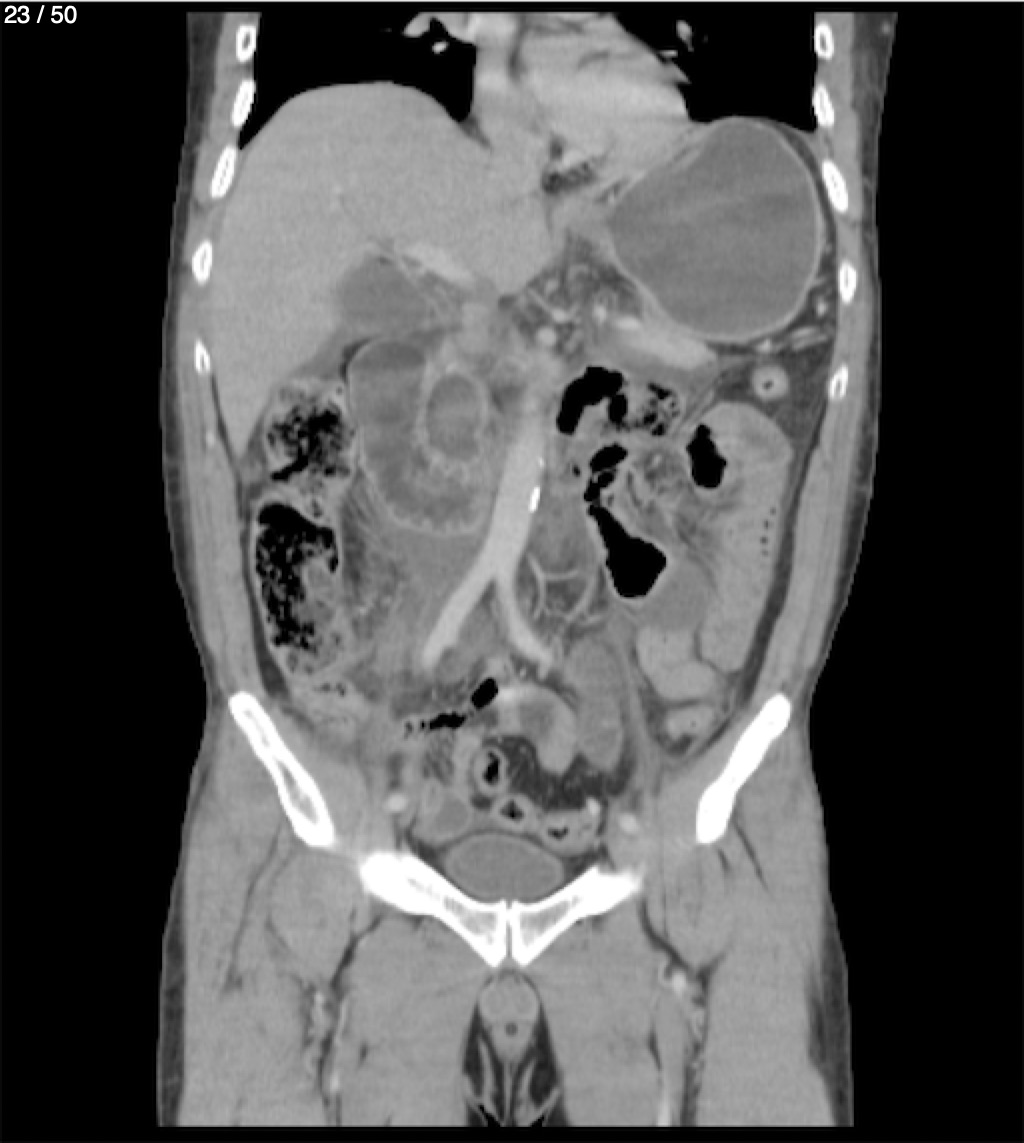

Alonso Victorio Ruiz 62A - T.C Abdomen Syc